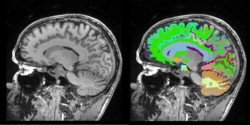

Pediatric MS Study

- Collaborator: Tanuja Chitnis PI (Brigham and Women's Hospital/Multiple Sclerosis Center), Alexander Zaitsev (Brigham and Women's Hospital/Surgical Planning Laboratory) and Massachusetts General Hospital

- Short description: Evaluate brain atrophy for pediatric MS Patients

- Image specification: 3 Tesla, Scanner: SIGNA HDx / GE MEDICAL SYSTEMS, 3D MPRAGE, Sagital Scans, TR/TI/TE=24/0/7 ms, pixel_xsize = 0.976600, pixel_ysize = 0.976600, fov = 250.009598, aspect = 1.535941, thick = 1.500000, space = 0.000000

- Used Task: MRI Human Brain